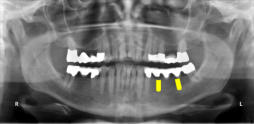

Beispiele für komplexe implantologische Versorgungen aus unserer Gemeinschaftspraxis

(Planung / Endversorgung -- als Röntgenaufnahmen)

C1

C2

C3